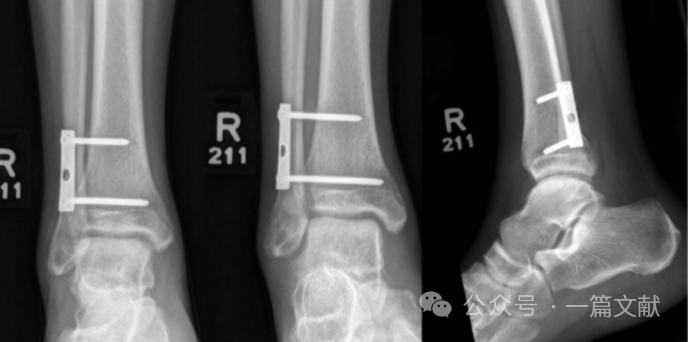

螺钉最终固定的踝穴位片与健侧相对比如下图:

2,中和钢板固定:相对于前述之螺钉固定,钢板固定有以下优点: 1) 此钢板起到类似于螺钉垫圈效果,将螺钉的压力更均匀分布在腓骨表面。2)钢板置于腓骨后外侧,可减少内固定引起的软组织激惹,以及更好的垂直切迹置钉。3)还可避免螺钉过于靠前或靠后拧入造成医源性骨折并最终导致内固定失效。如下图:2枚3.5mm螺钉固定在三孔钢板的两端,行三皮质固定。从左到右依次为前后位,踝穴位,侧位片。